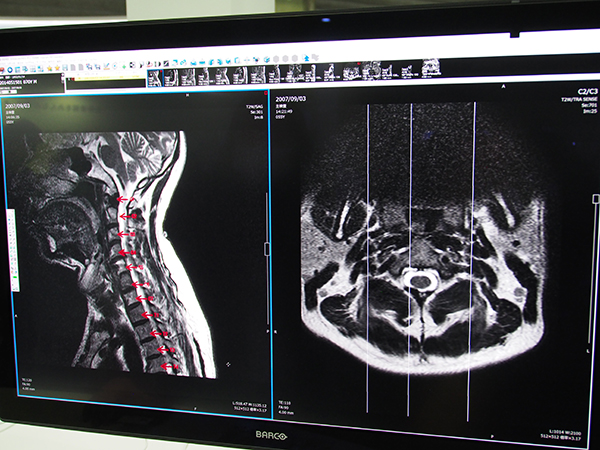

今回のバージョンアップでは,脊椎ラベリングをアノテーションとして保存できる機能が追加された。サジタル画像に対して脊椎にマニュアルでラベリングを行うと,脊椎番号がアノテーションとして保存され,アキシャルなど別の断面で表示したときにも,連動して脊椎番号が表示され読影をサポートする。ラベリング方法はユーザーごとに設定でき,ラベリングを開始する脊椎とラベリングの方向(C1から尾側へ,T12から頭側へなど)をプリセットしておくことで,脊椎を指定していくだけで自動的に番号が振られる。

「EV Insite R」に追加された脊椎ラベリングをアノテーションとして保存する機能

アノテーションは各断面に連動し,アキシャル表示では右上に脊椎番号が表示され読影を支援する